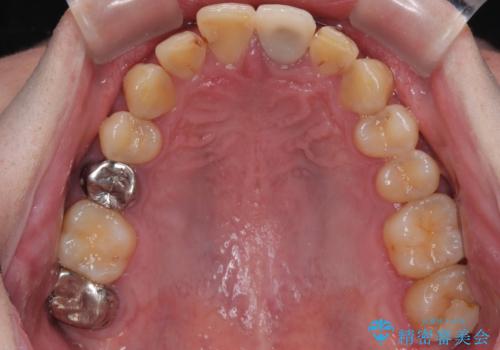

拡大鏡視野下で保険のプラスチック(コンポジットレジン)、虫歯、左上1の被せものを除去し、オールセラミッククラウンに適した形にしました。

歯と歯茎の間に圧排糸と言われる糸を入れてシリコーン印象材にて型どりをしました。